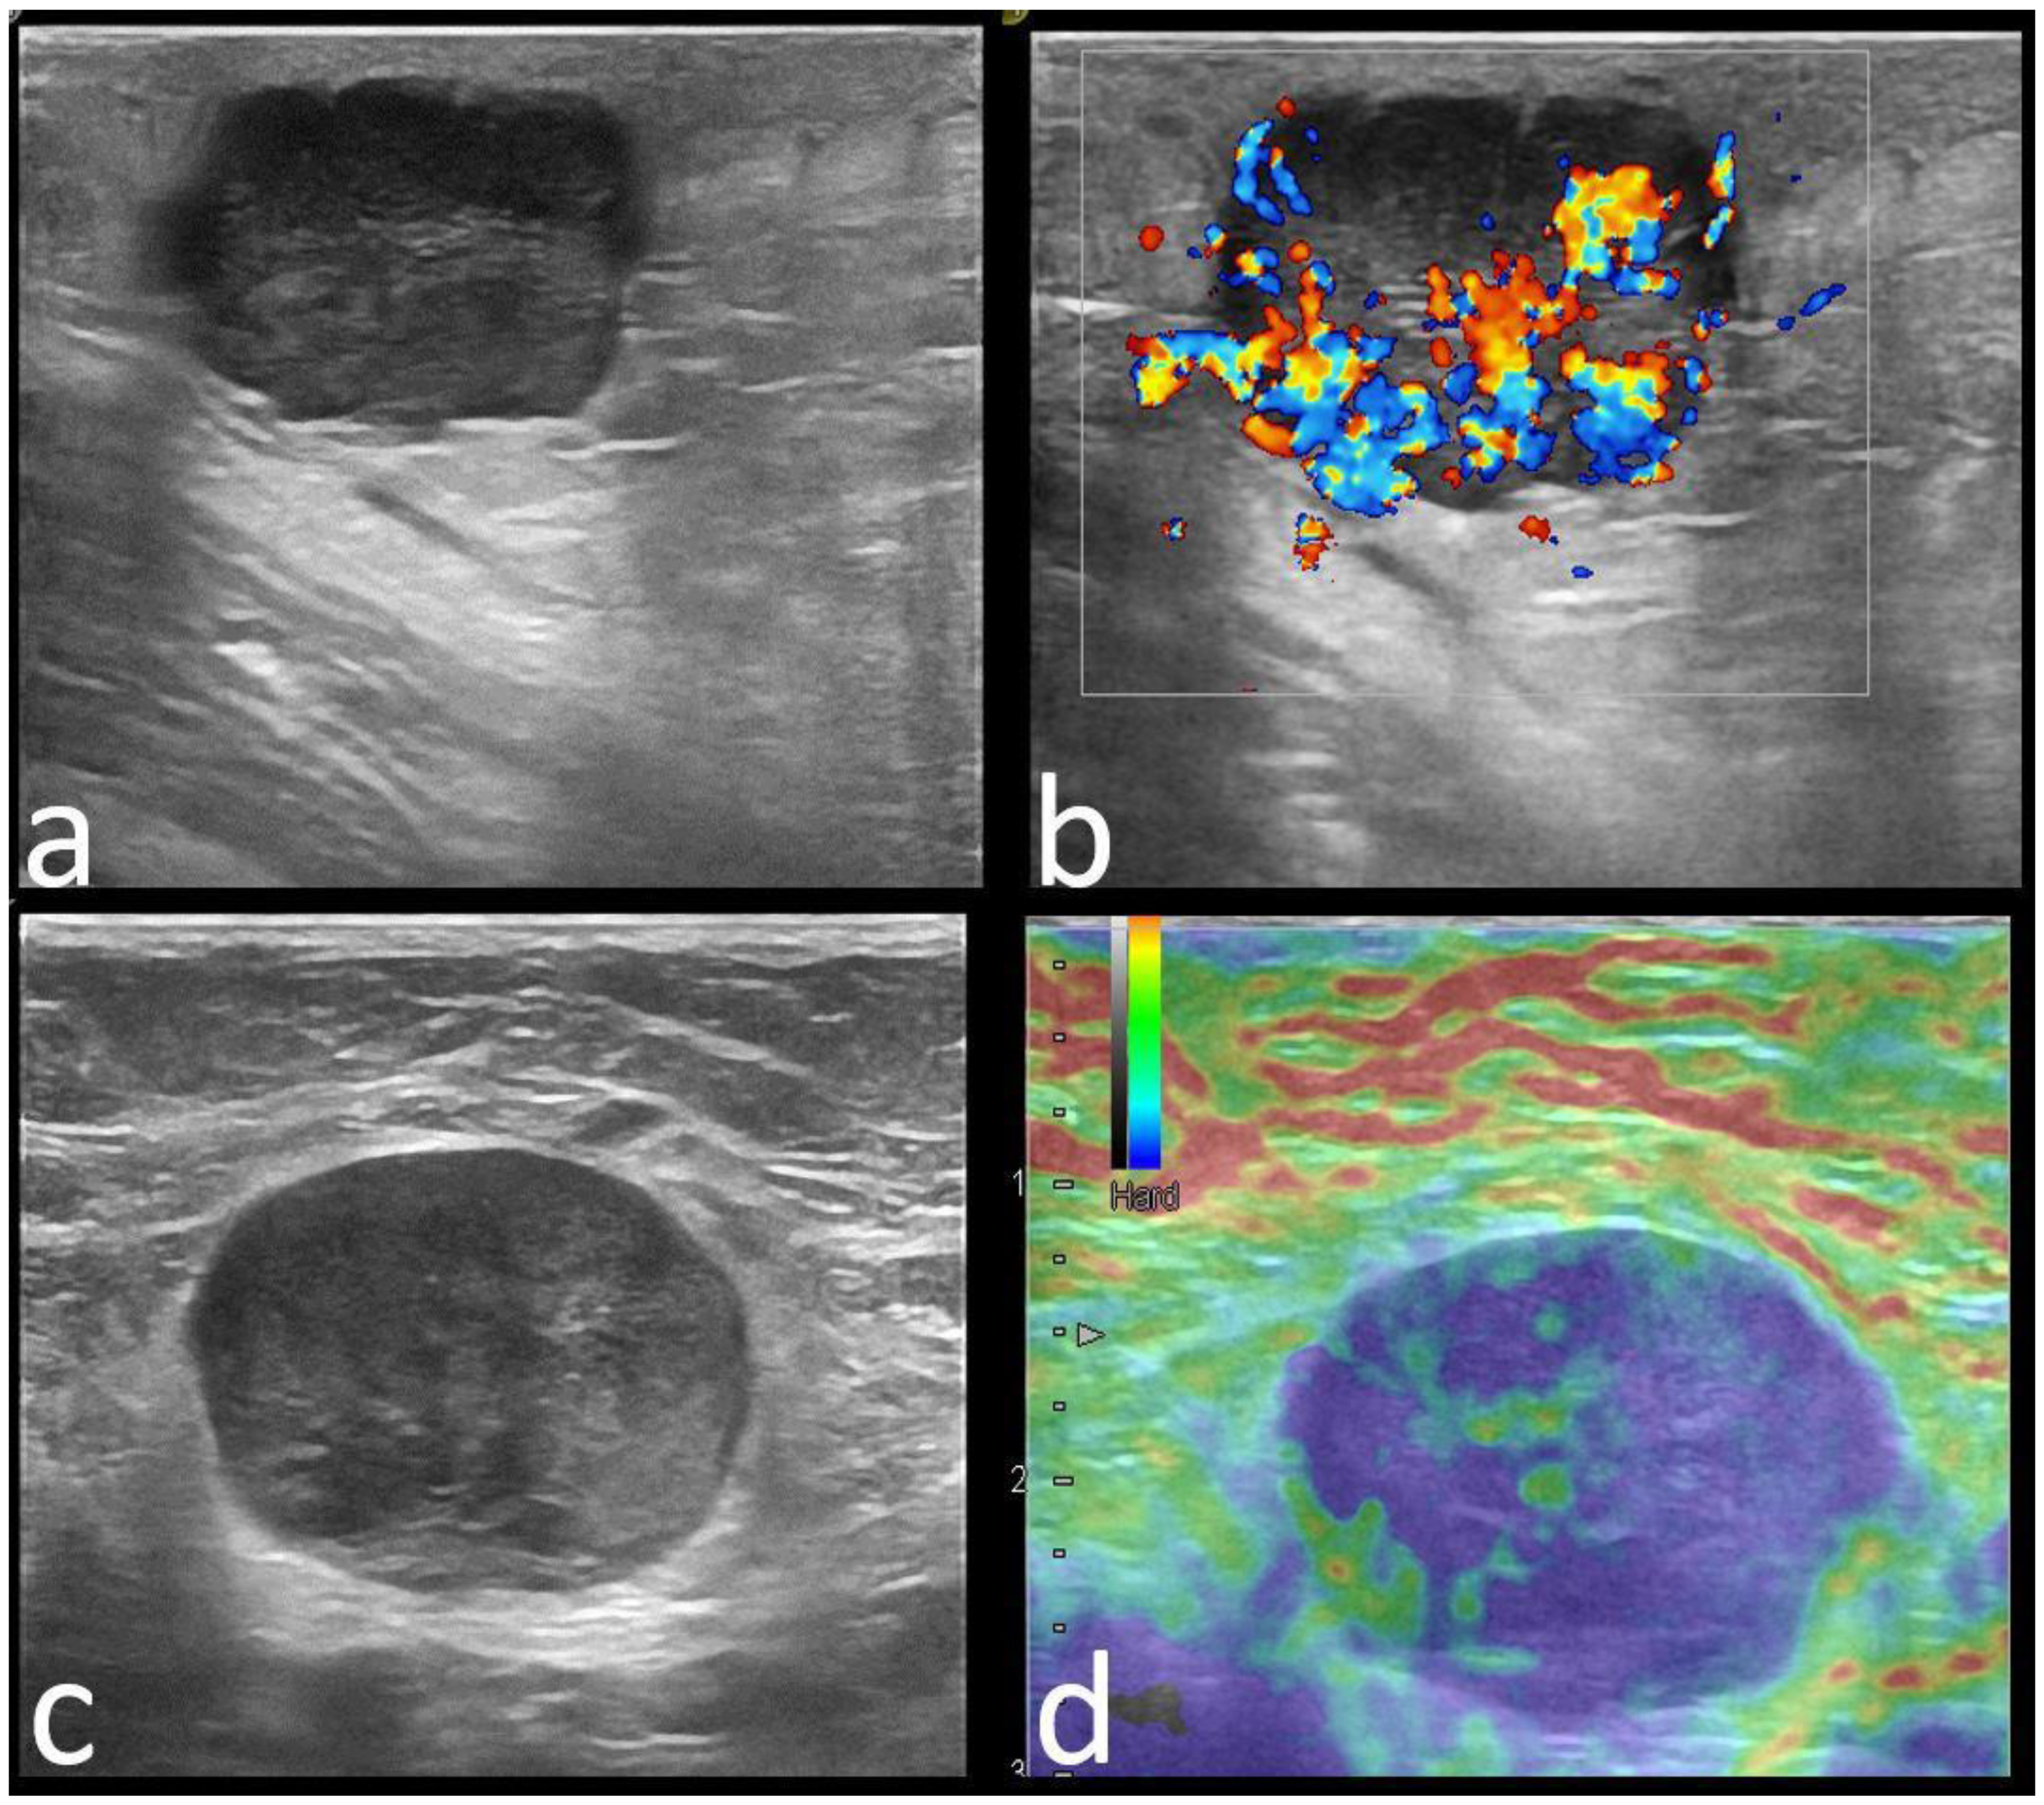

| Echo pattern | 0.000 | ||

| Hypoechoic | 57 (58.2) | 100 (70) | |

| Heterogeneous | 36 (36.7) | 19 (13) | |

| Isoechoic | 5 (5.1) | 26 (17) | |

| Posterior features | 0.000 | ||

| None | 39 (39.8) | 71 (49) | |

| Enhancement | 27 (27.6) | 12 (8.3) | |

| Shadowing | 15 (15.3) | 54 (37.2) | |

| Combined | 17 (17.3) | 8 (5.5) | |

| Strain Elastography | 0.029 | ||

| Soft | 40 (40), 9 BGR | 30 (20.6), 1 BGR | |

| Hard | 58 (60) | 115 (79.3) | |

| Margins | C (20/29) | NC (11/15) | NC (11/15) | NC (11/15) | C (5/7) | NC (5/6) | C (3/3) | NC (3/3) |

| Echo pattern | Hypoechoic (19/29) | Hypoechoic (9/15) | Heterogeneous (5/15) | Hypoechoic (11/15) | Hypoechoic (4/7) | Heterogenous (3/3) | - | Hypoechoic (2/3) |

| Posterior features | Enhancement (16/29) | Absent (9/15) | Shadowing (6/15) | Enhancement (6/15)/Combined pattern (5/15) | No posterior (4/7) | - | Enhancement (2/3) | - |

| Associated features | Hyperechoic rim (6/29) Soft elastography (11/29) | Calcifications (7/15) Hard elastography (12/15) | Calcifications (7/15) | - | - | Calcifications (3/6) Hyperechoic rim (3/6) | - | Calcifications (2/3) Architectural distortion (2/3) |